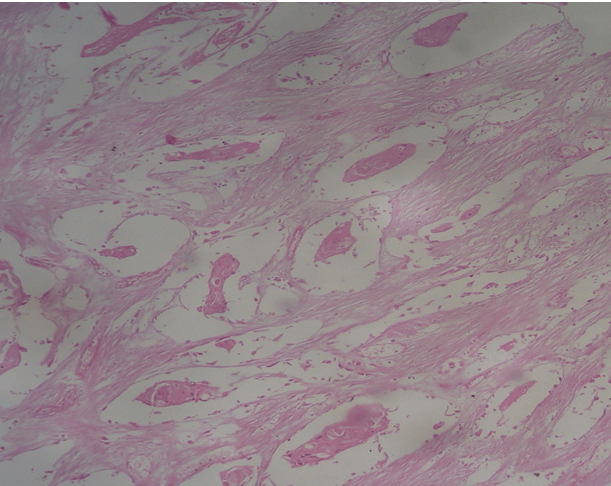

Microscopic examination revealed sheets of malignant keratinized squamous cells separated by fibrous stroma (Figure 3). Extensive keratinization and cancer pearl formation was noted (Figure 4). All lines of resection were negative for tumor.

Figure 3: Sheets of malignant keratinized squamous cells.

Cursor on image to zoom/Click text to open image

Figure 4: Slide showing cancer pearls and extensive keratinization.